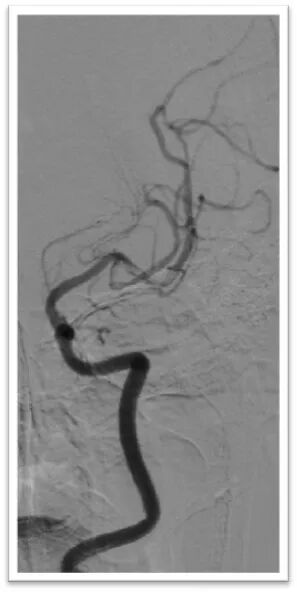

取栓后造影显示左侧颈内动脉血流恢复,管腔内局部可见白色血栓影,左侧颈外动脉闭塞,左侧大脑中动脉M2段上干长节段血栓影,下干闭塞,动脉缓慢推注替罗非班10ml,造影显示颈内动脉管腔通畅,大脑中动脉下干血流恢复,上下干仍可见血栓。

微导丝引导微导管顺利置于左侧大脑中动脉上干,半释放6-30mm支架,停留5分钟后完全取出血栓,造影显示左侧大脑中动脉血流完全恢复,mTICI:3级。